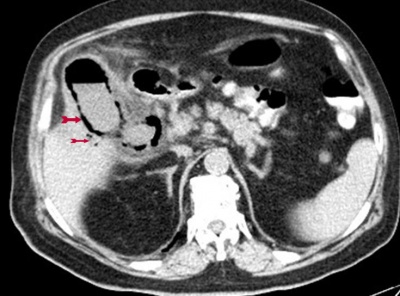

- ב- CT אפשר לראות כיס מרה עם דופן מעובה, אבנים ולעיתים אוויר בדופן המרה Ephysemtous cholelithiasis (תצלום 39.8).